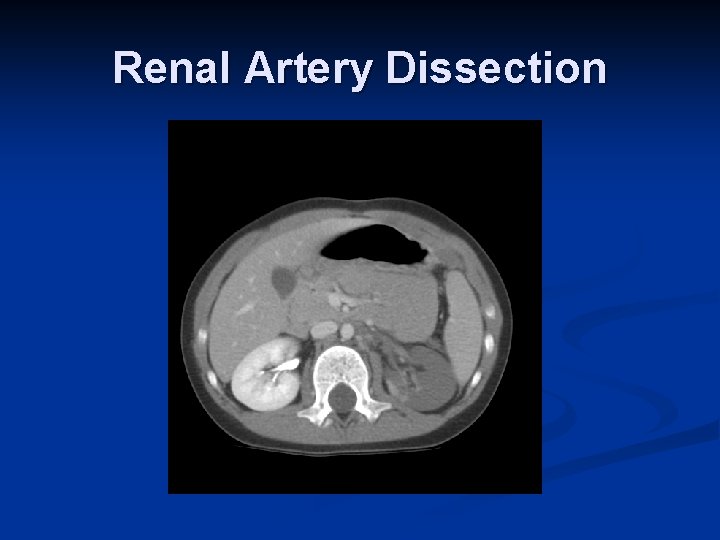

Role of Interventional Radiology n Embolization Spleen n Liver n Pelvis n n Angioplasty + Stent n n Renal artery dissection Stent n Thoracic aortic injuries

Renal Artery Dissection